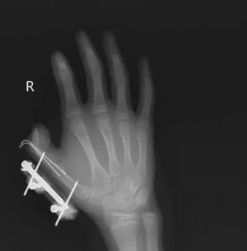

前段時間,湖南的一名 14 歲的小孩在爸爸網(wǎng)購冰激凌的箱子里發(fā)現(xiàn)了用于冷藏的干冰,以為是玩具,便捏在手里反復(fù)搖晃。結(jié)果密封袋里的干冰突然爆炸,小朋友的右手瞬間鮮血直流,拇指虎口處被撕開一道約 10 厘米的傷口,拇指骨折。